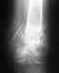

Re: Перелом в/3 голени. Аппарат Илизарова

2. Конечно, есть. И перелом тяжелый, то есть пострадало кровоснабжение кости, и не идеальное положение фрагментов.

3. Конечно, существуют - но зачем Вам "средняя температура по больнице"? Если показанный снимок - свежий, то не факт, что кость вообще срастется только при дальнейшем ожидании, без каких-то новых активных действий.

4. Искать надо клинику, где могли бы сделать закрытый интрамедуллярный остеосинтез, т.е. ввести внутрь кости металлический стержень (в отношении инфекции безопаснее бесканальный титановый), запертый винтами. Это даст возможность немедленно вернуться к обычной жизни. Ходить, работать. Запаса прочности у "правильного" стержня хватит до сращения. Никаких открытых вмешательств на зоне несращения при этом не нужно. В Белоруссии уже должна быть доступна эта методика. Если ближе не найжете - приезжайте к нам в институт, у нас опыт несколькиз сотен таких операций именно в ситуации, подобной Вашей.